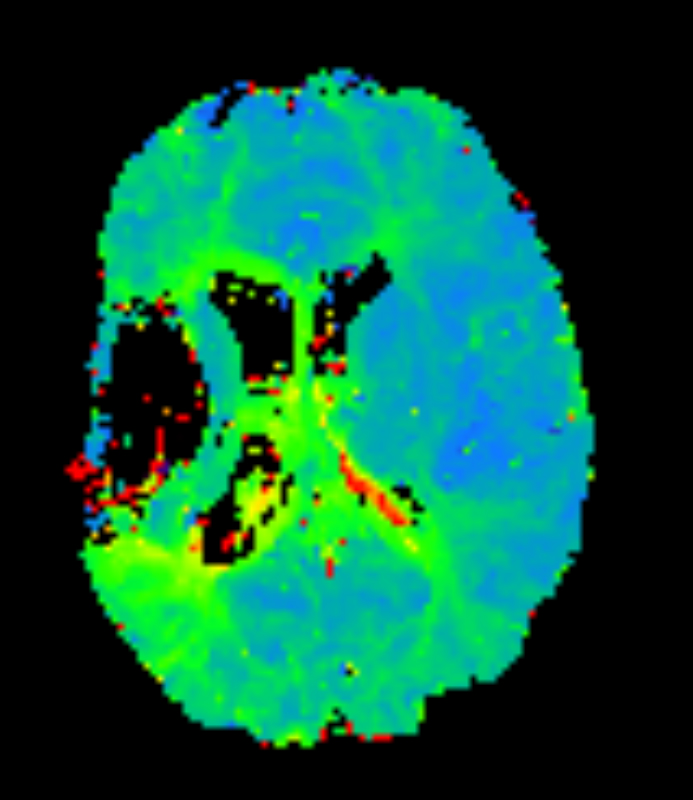

Axial T2* Perfusion - TTP